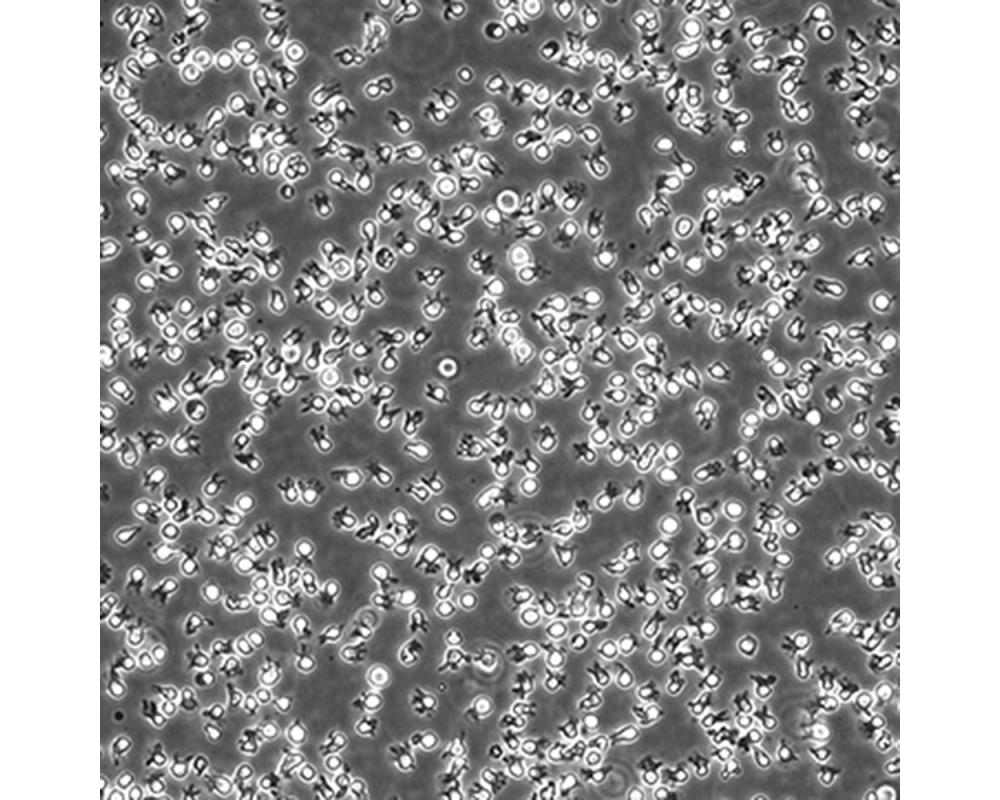

中文名稱 人彌漫大B細胞淋巴瘤細胞

組織來源 彌漫大B細胞淋巴瘤;男性

生長特性 懸浮

培養基 IMDM,90%;FBS,10%;雙抗。

傳代方法 Maintain cultures at a cell concentraion between between 1 X 10(5) and 1 X 10(6) viable cells/ml.

培養條件 Atmosphere: Air, 95%; CO2, 5%。Temperature: 37℃